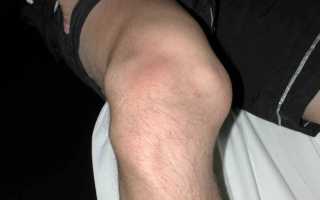

Внешний симптом.

5. Отек в области колена, вызванный кровоизлиянием в сустав или синовитом.

Симптомы вывиха коленной чашечки, если он не острый, проявляются «провалом» в суставе при сгибании ноги. Острая травма надколенника сопровождается болью, ограничением движений и отеком из-за гемартроза.